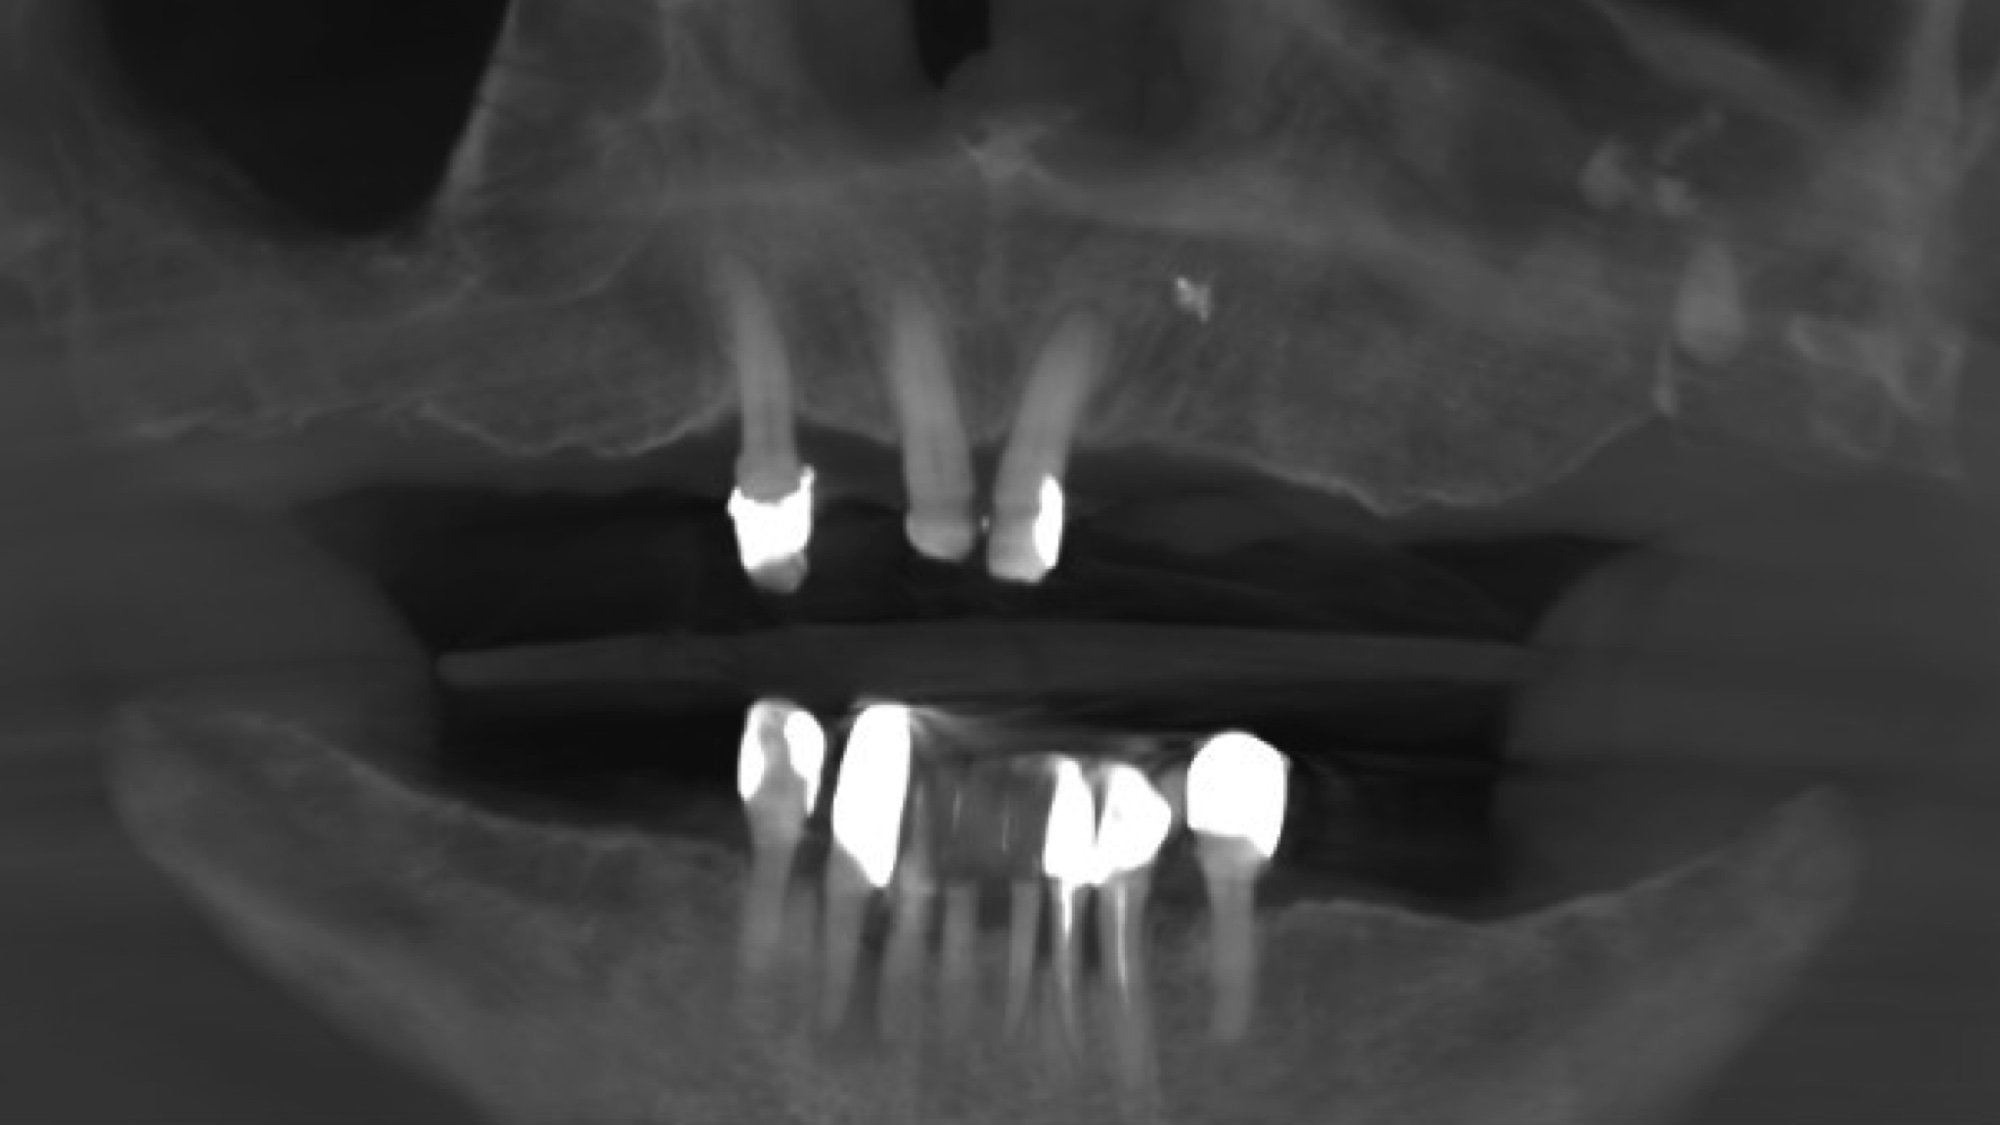

O możliwości leczenia decyduje również wynik badania klinicznego stanu zdrowia jamy ustnej pacjenta w czasie której ocenia się tkanki miękkie, zęby, tkanki przyzębia, zgryz oraz rozległość braków zębowych. Dodatkowe informacje niezbędne do kompleksowej diagnostyki uzyskujemy za pomocą badania tomografii komputerowej 3D, które szczegółowo obrazuje ilość i jakość tkanki kostnej mającej stanowić podłoże dla wszczepów.

Decyzję o przeprowadzeniu zabiegu odbudowy kości podejmujemy po uprzednim przeprowadzeniu diagnostyki radiologicznej tomografii komputerowej CBCT.

Na podstawie tego trójwymiarowego zdjęcia 3D dokonujemy precyzyjnych pomiarów kości w różnych odcinkach, jak również odległości od sąsiadujących zębów i struktur anatomicznych jak dno zatoki szczękowej czy kanał żuchwy.

CBCT przed i po augmentacji